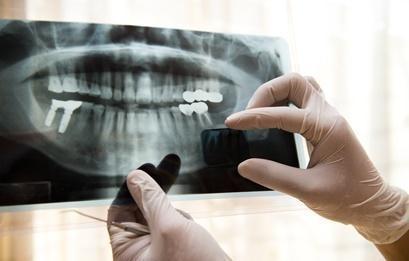

De asemenea, oferim radiografii panoramice, care permit vizualizarea in ansamblu a tuturor dintilor si a elementelor maxilo-faciale inconjuratoare, cu ajutorul aparatului ultraperformant, cu doza extrem de scazuta de radiatii.

Pentru copii, se poate realiza ortopantomografie pediatrica, cu scopul de a vizualiza mugurii dintilor permanenti.

Cabinetul nostru va ofera imagini clare, cele mai mici doze de radiatii precum si preturi mici pentru pacientii care necesita astfel de investigatii.

Radiografiile dentare digitale au o calitate inalta, ajutand la diagnosticarea afectiunilor de sanatate orala inca din stadiu incipient.